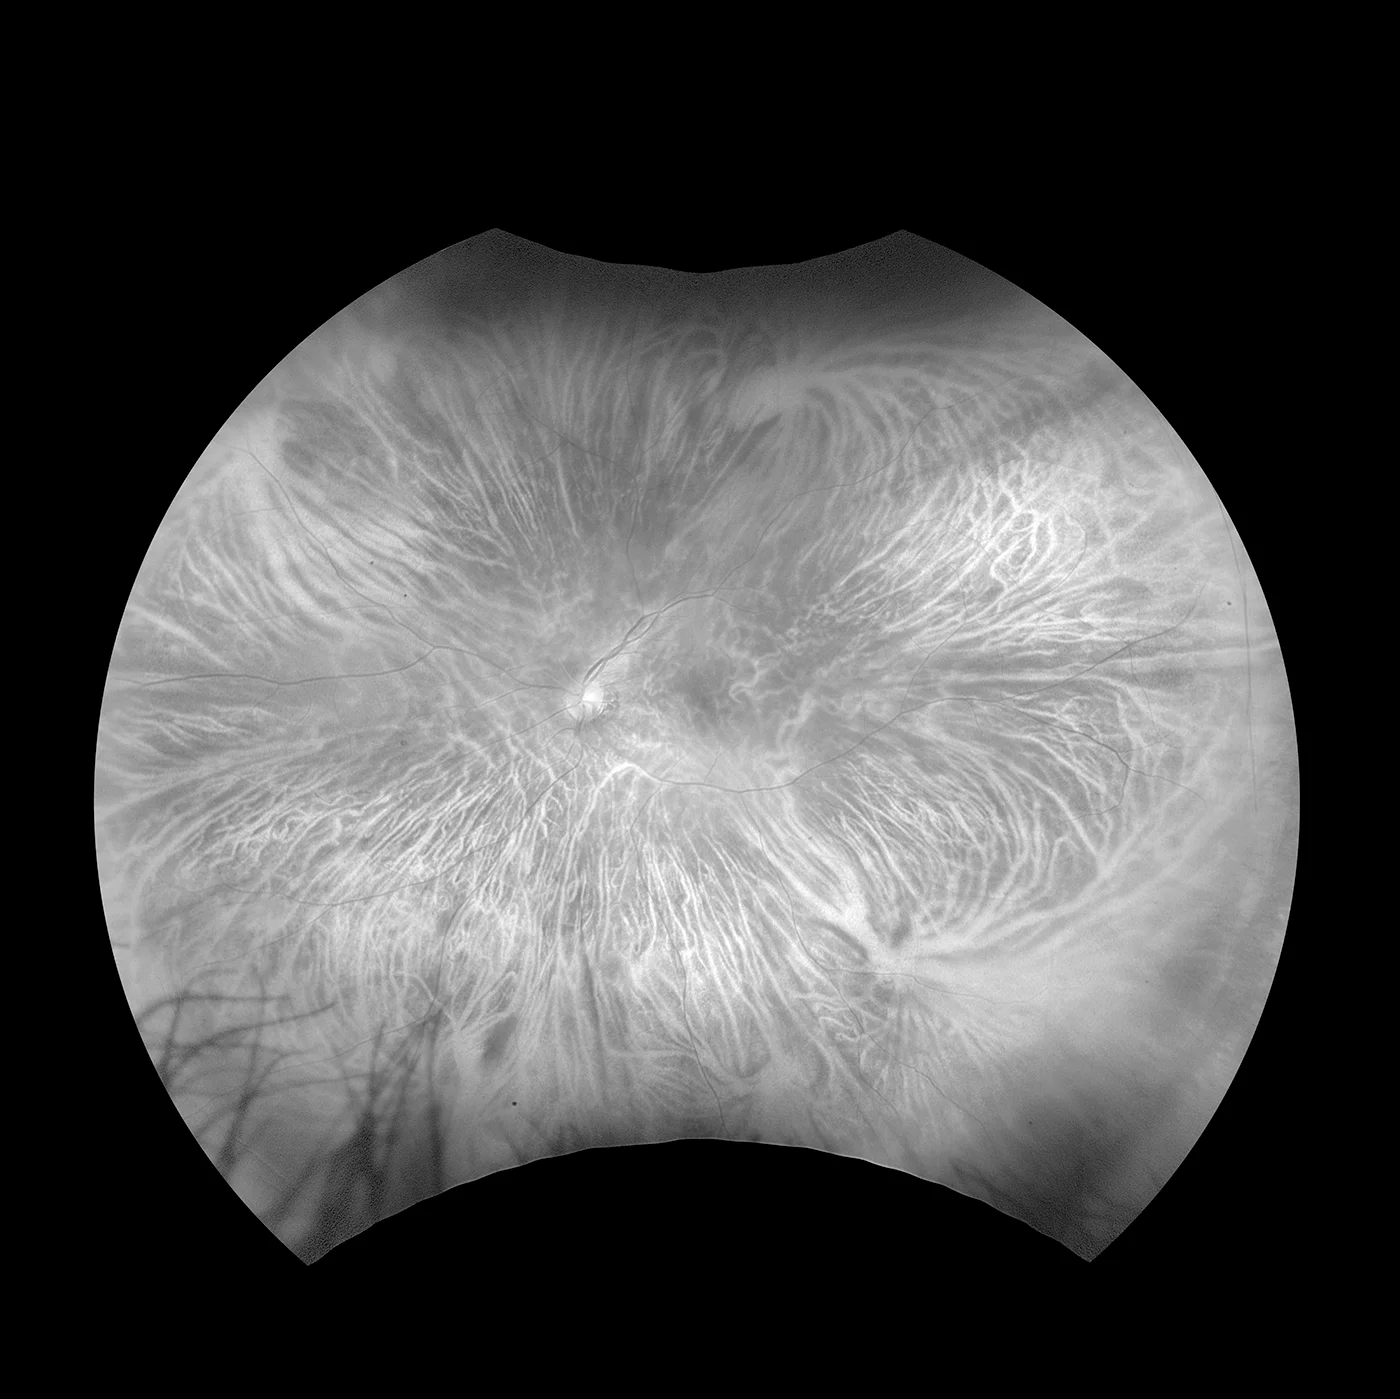

- Autofluoreszenz